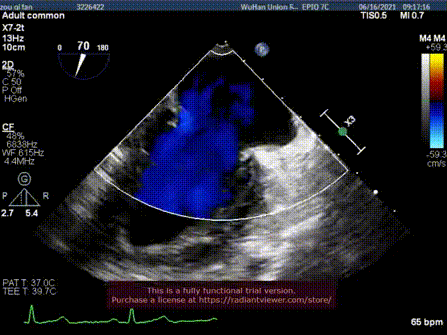

术前超声

手术过程